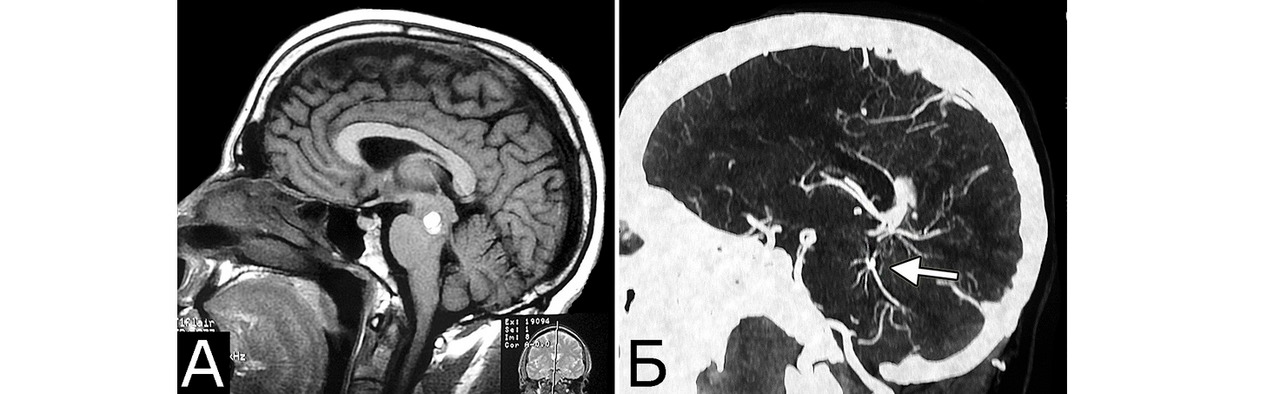

Мр картина венозной ангиомы левой гемисферы мозжечка - 96 фото